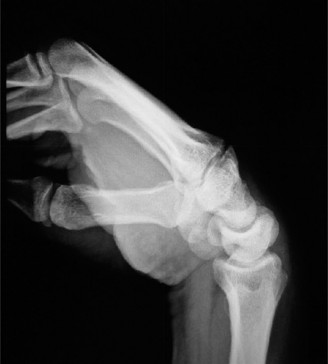

For the second patient, standard PA radiographs immediately reveal the diagnosis. We observe the classic Terry Thomas sign—a widening of the scapholunate interval greater than 3 mm. Furthermore, the lateral radiograph demonstrates a Dorsal Intercalated Segment Instability (DISI) deformity, characterized by a radiolunate angle greater than 15 degrees (lunate extended) and a scapholunate angle greater than 60 degrees.

Advanced imaging, particularly Computed Tomography (CT), is highly beneficial for preoperative templating. A fine-cut CT scan accurately maps the extent of the degenerative changes. In scapholunate advanced collapse (SLAC), arthritis follows a highly predictable, sequential pattern. It begins at the radial styloid-scaphoid articulation (Stage I), progresses to involve the entire radioscaphoid fossa (Stage II), and eventually encompasses the capitolunate joint as the capitate migrates proximally into the widened SL gap (Stage III). Notably, the radiolunate joint is universally spared in SLAC wrist due to the concentric, congruent nature of the lunate fossa and the preservation of the short radiolunate ligaments.